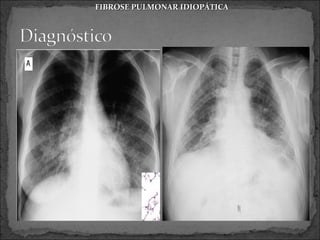

 Radiografia

 Infiltrados reticulares ou reticulonodulares bilaterais

em HTXs

 Faveolamento: cistos